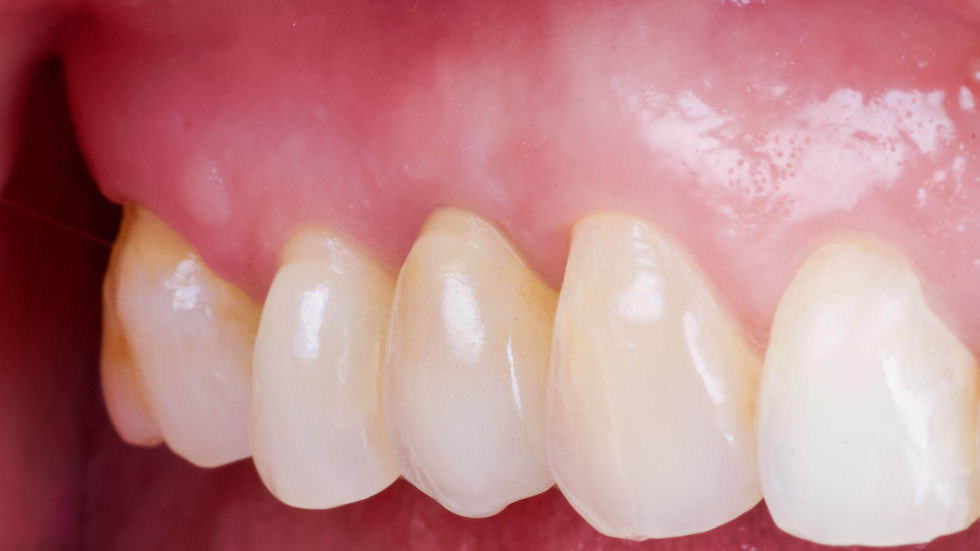

Healing at 8 months. Tissues, completely healed, are stable and mature. The formation of thick papillae and the neovascularization that starts from the intramucosal neck of the Prama RF implant can be appreciated.